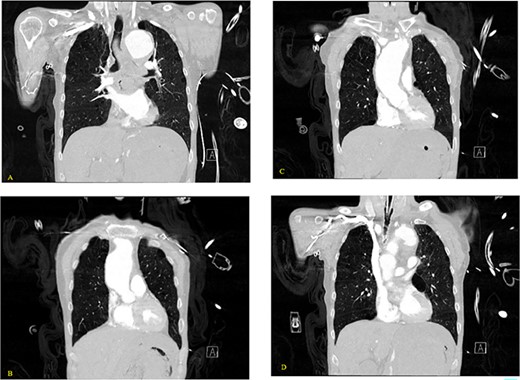

A 59-year-old male with no known previous medical history presented to a Level 1 trauma center after being discovered by EMS in a large volume of red blood. The event was unwitnessed by bystanders, so it was assumed that the mechanism was a traumatic fall with a resulting head bleed. During transportation patient lost pulses but returned to spontaneous circulation after cardiopulmonary resuscitation. The patient’s initial vital signs in the trauma bay were a blood pressure of 129/40 mmHg, a heart rate of 101 beats/min, and a Glasgow Coma Score of 3. The head was bandaged by EMS with red blood sticking to the patient’s hair, ears, and face. Upon unwrapping of the patient’s bandaged head, there was no source of bleeding nor was any trauma identified to the body. The patient was intubated and an orogastric tube was inserted with immediate drainage of 2L of bright red blood. The initial differential diagnosis was trauma in origin, including a basilar skull fracture with ingestion of blood or blunt abdominal trauma. Sonography identified no signs of internal peritoneal bleeding. Chest X-ray revealed large dilation of the thoracic aorta (Fig. 1). CT of the chest with IV contrast showed aneurysmal dilation of the ascending and descending thoracic aorta with max diameter of 65 mm, AEF at the level of pulmonary artery bifurcation and contrast extravasation into the esophagus and stomach (Figs 2–4). Octreotide was given and a massive transfusion protocol (MTP) was initiated with transfusion including 2 units of whole blood and 15 units of RBCs. Cardiothoracic surgery and interventional radiology were called to evaluate the patient; however, massive blood loss ultimately led to a myocardial infarction and the patient expired 75 min after admission.

(A–D) Coronal CT chest with contrast reveal the descending aortic aneurysm of at least 6.5-cm diameter. Deep ulceration in the descending aorta at approximately the level of the pulmonary artery bifurcation. The ulceration has eroded into the esophagus. Extravasation of contrast is observed from the ulceration into the esophagus.